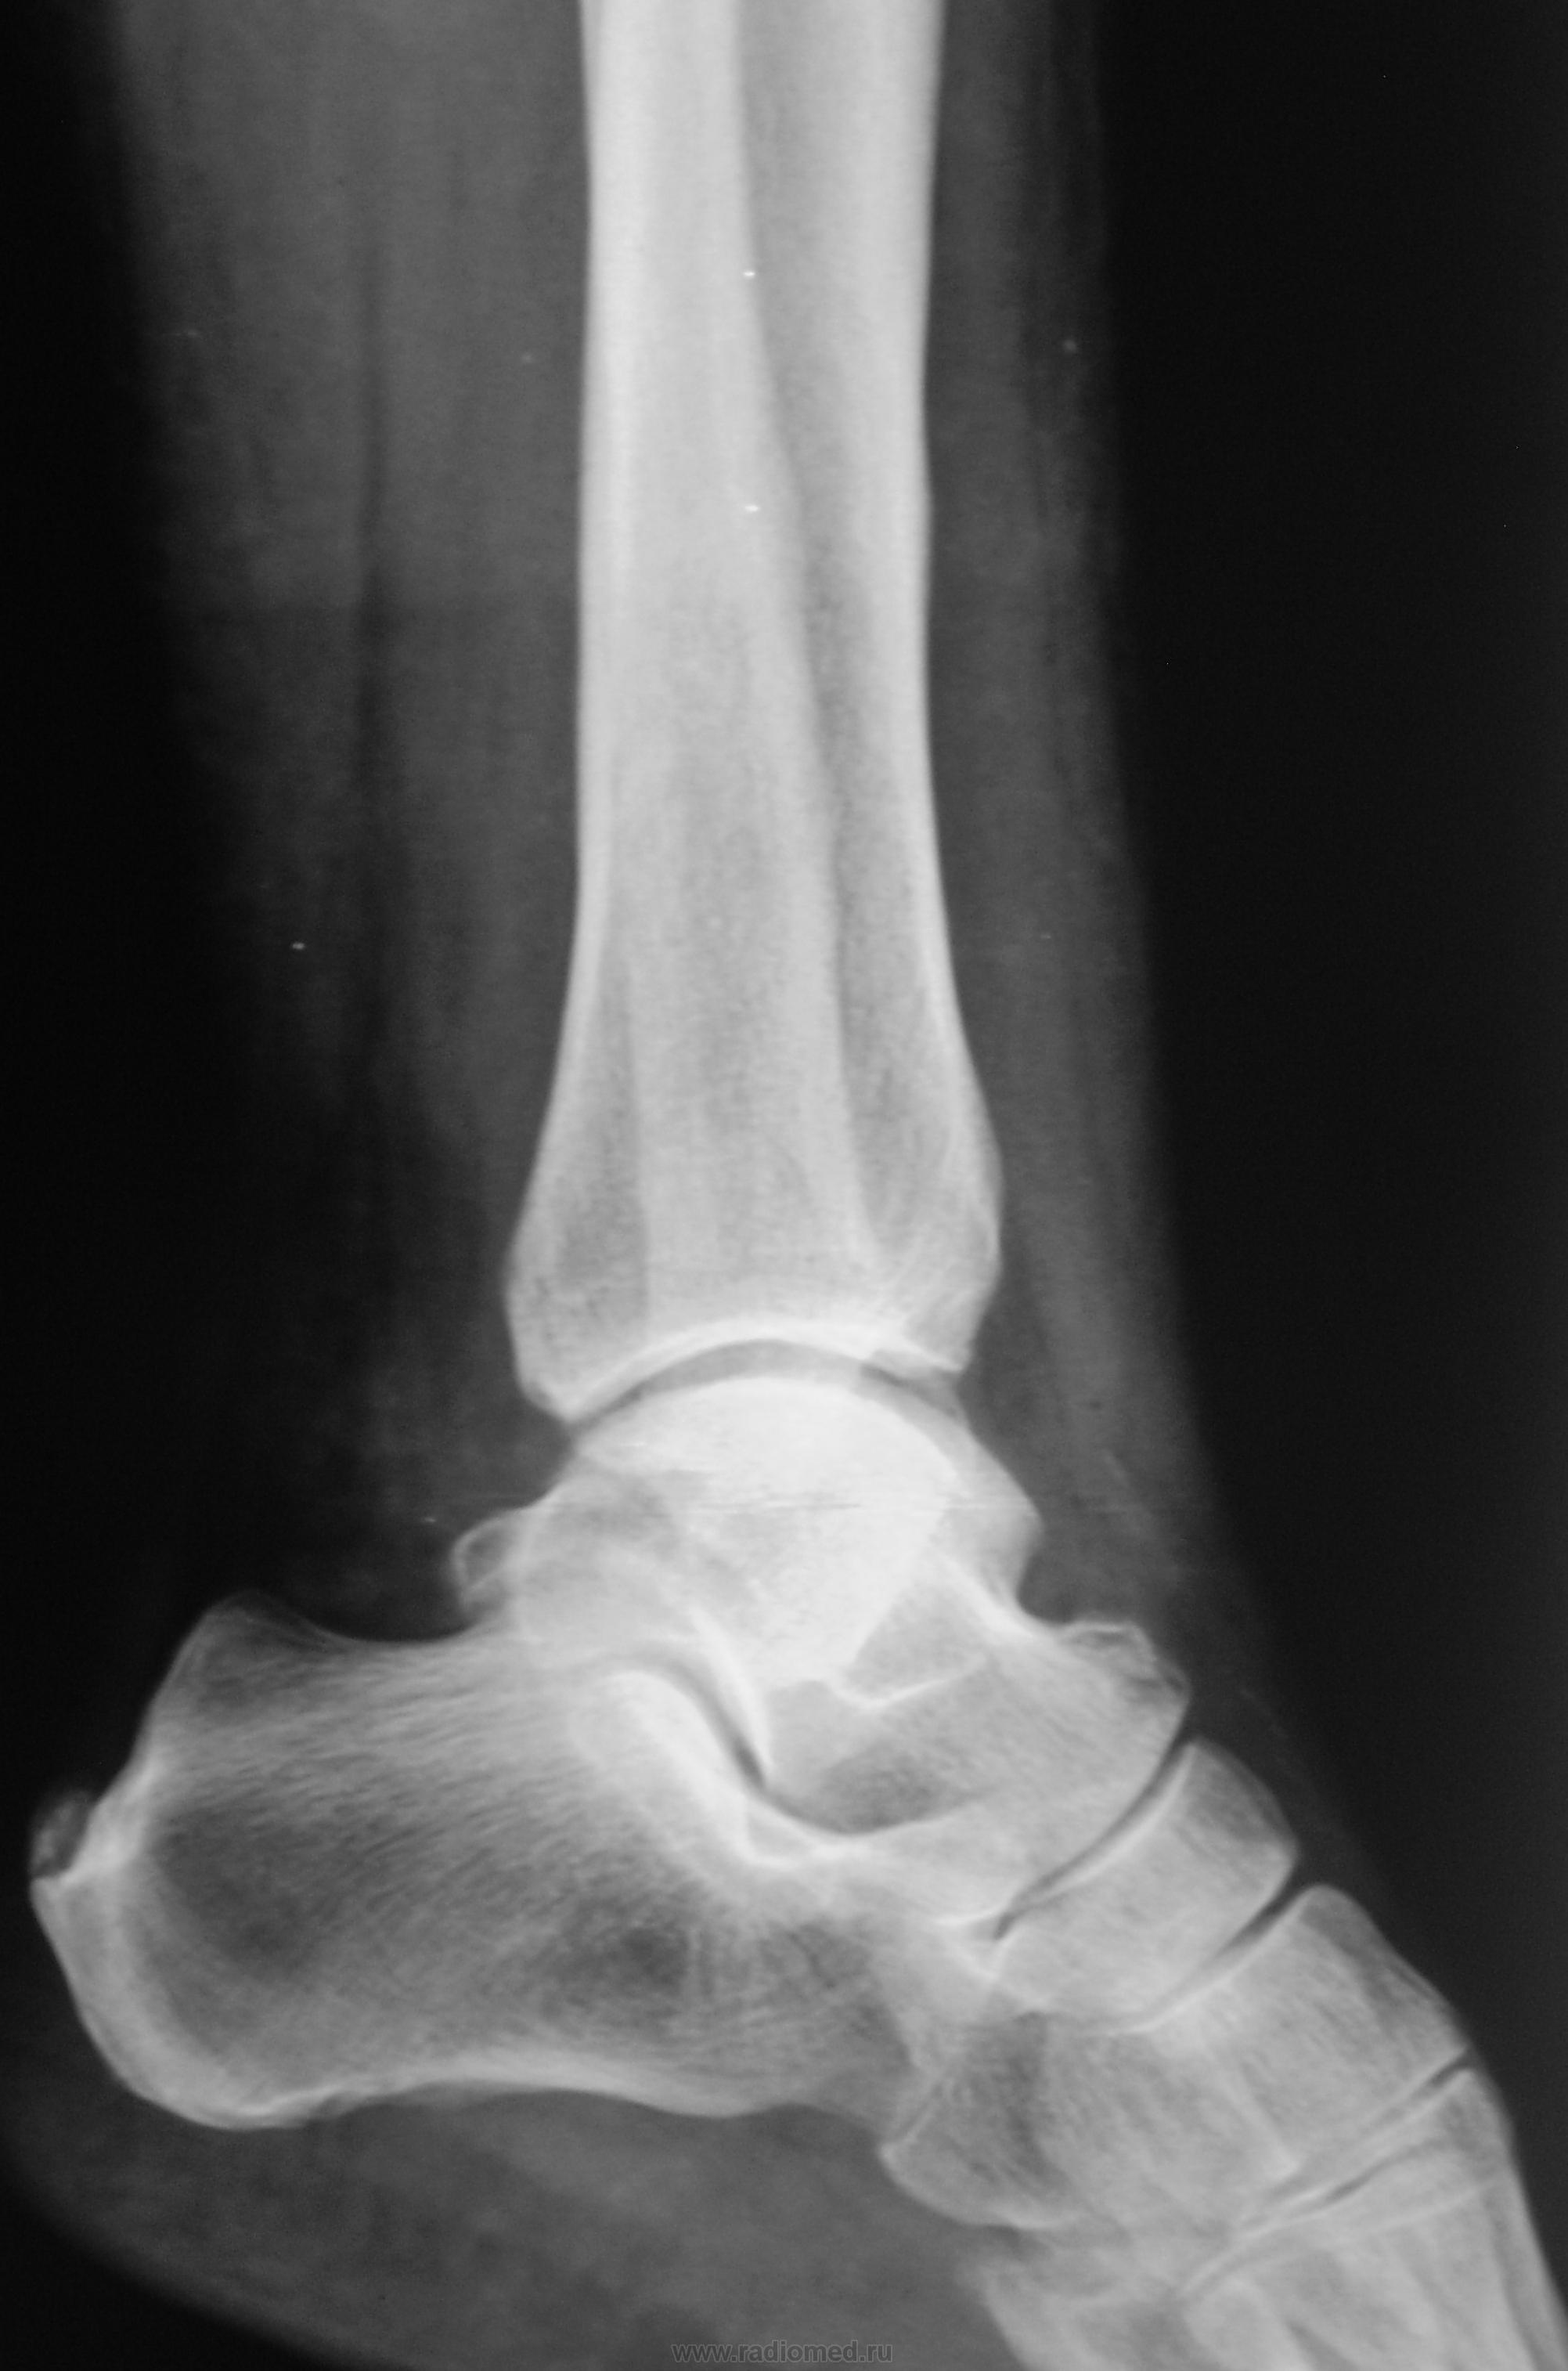

Краевой перелом наружной лодыжки? Интересен механизм травмы.

Перелом наружной лодыжки. Но механизм интересно знать. Футболист, гонитель жён или гандболист и т.д.

Тогда отрывной перелом за счет перерастяжения сухожилия.

перелом то обычный, наружняя лодыжка, а вот н\3 м\б кости подвздута и периостит б\б кости или мне это кажется)

наруж. лодыжки самый банальный ( без смещения).Таких в пору гололёда в день по несколько штук видим. Смутил переостит по передней поверхности малоберц. к.